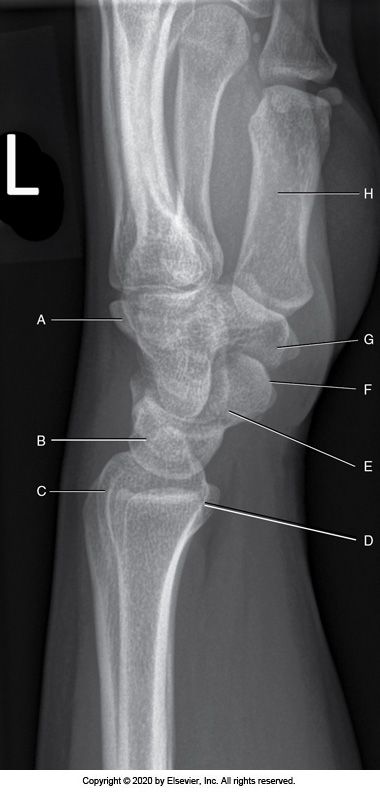

Identify the labeled anatomy "B" in the image below:

Radial styloid